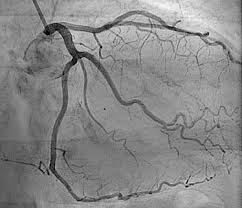

Real-time AI Guidance for Complex Vascular Interventions

Creating an AI system that provides dynamic guidance during complex vascular procedures, predicting optimal tool paths and identifying potential complications before they occur.